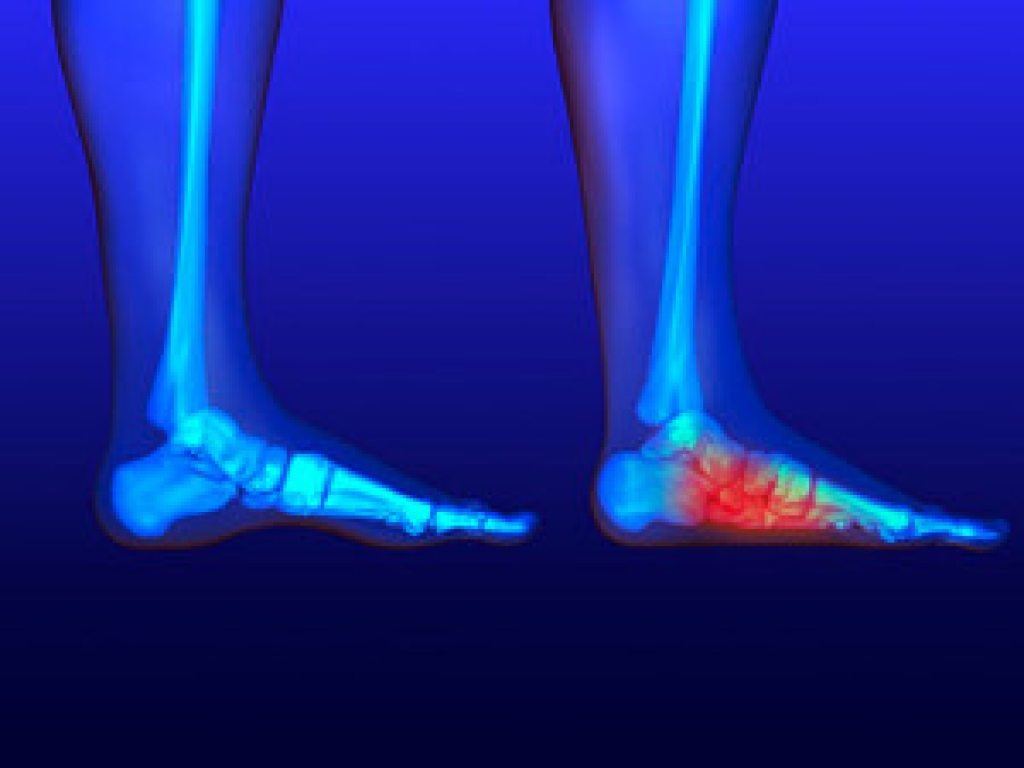

If you are experiencing a hard lump on the bottom of the heel, you may have what is referred to as a heel spur. It generally comes from calcium deposits and is typically caused by injuries or strains to the foot. If the heel endures pressure, possibly caused by jogging, excess weight, or shoes that fit poorly, heel spurs may gradually develop, often causing discomfort and pain. Other causes of this condition may include having flat feet, standing the majority of the day, or experiencing less flexibility in the plantar fascia which affects the stability of the heel. Possible treatment options may include wearing shoes with a cushioned heel or custom made orthotics. Please schedule a consultation with a podiatrist if you are affected by heel spurs and would like more information.

Heel spurs are formed by calcium deposits on the back of the foot where the heel is. This can also be caused by small fragments of bone breaking off one section of the foot, attaching onto the back of the foot. Heel spurs can also be bone growth on the back of the foot and may grow in the direction of the arch of the foot.

The pain associated with spurs is often because of weight placed on the feet. When someone is walking, their entire weight is concentrated on the feet. Bone spurs then have the tendency to affect other bones and tissues around the foot. As the pain continues, the feet will become tender and sensitive over time.